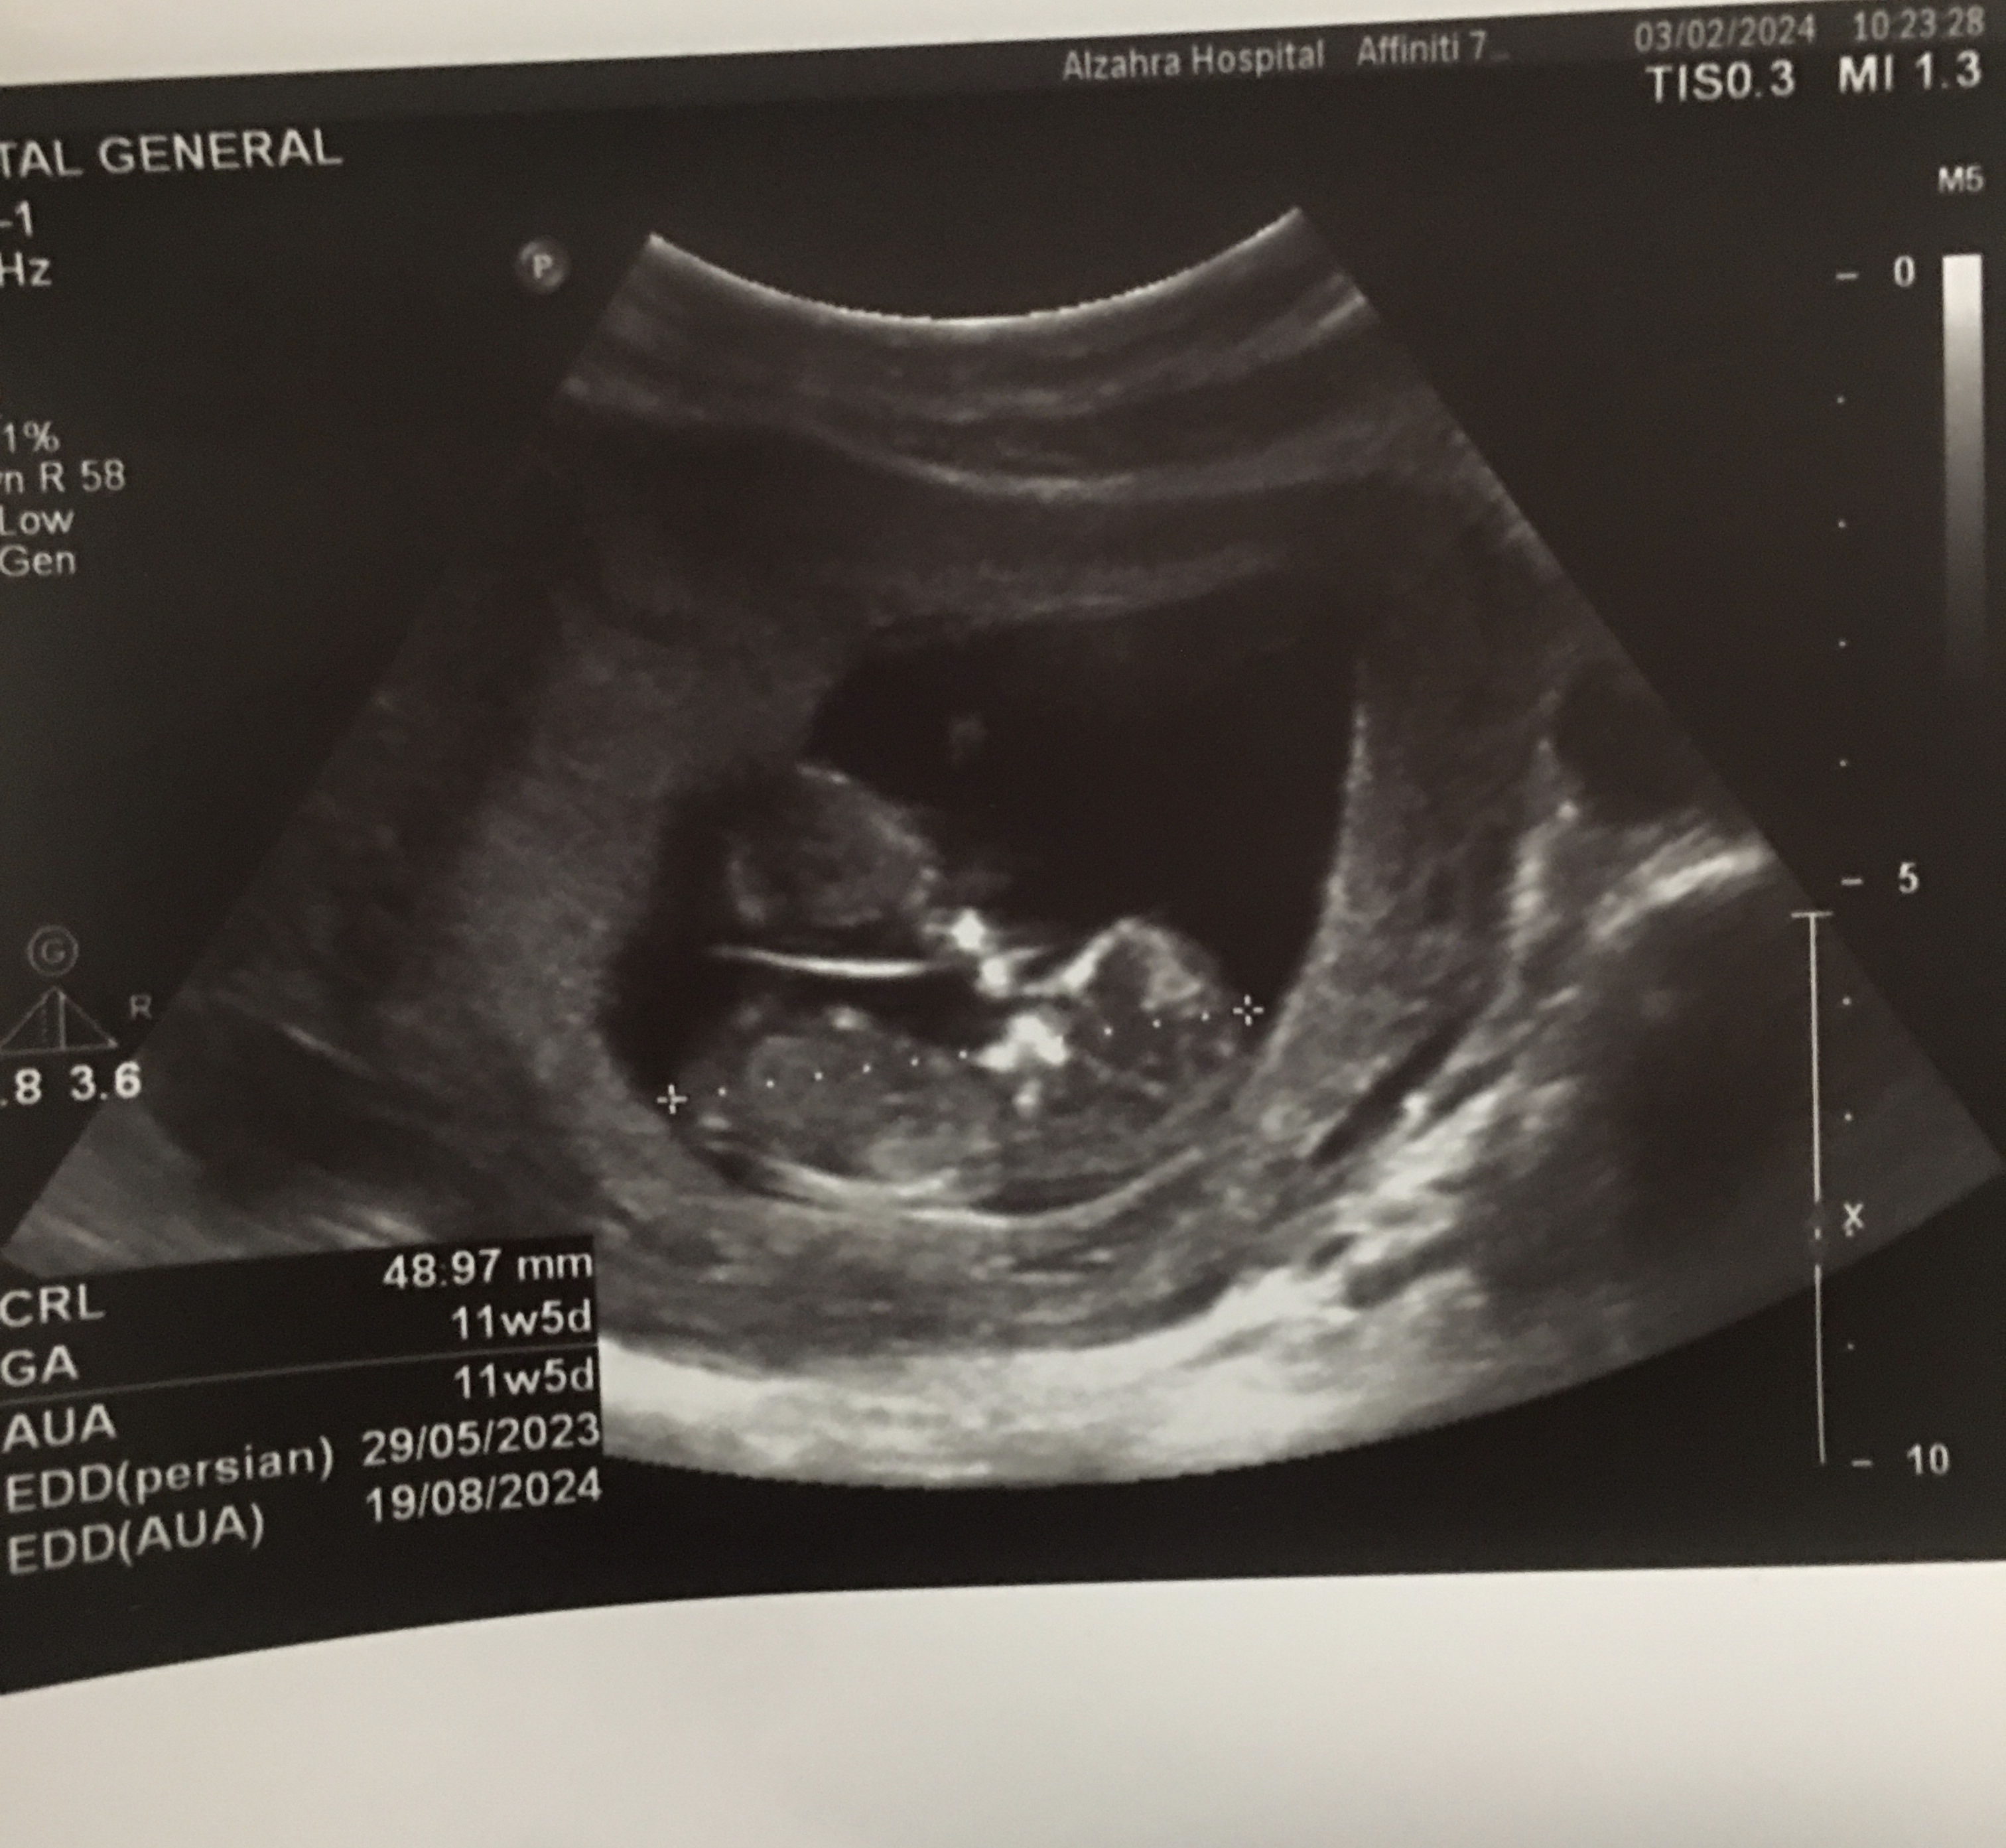

msal مدیر استارتر عضویت: 1401/06/14 تعداد پست: 545 عنوان خانومای وارد میتونین جنسیت دوقلوهای منو حدس بزنین😊 300 بازدید | 19 پست میشه بگین ممنون 1402/11/14 | 16:17 0 نفر لایک کرده اند ... گزارش تاپیک نامناسب